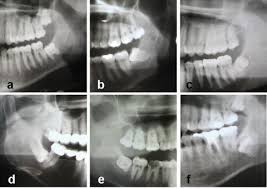

In fällen, in denen alle vier weisheitszähne in einer sitzung entfernt werden sollen, wird eine vollnarkose erwogen. Wenn ein weisheitszahn mit 25 jahren noch nicht da ist, sollte man ihn entfernen. Weisheitszähne, die noch im zahnfleisch liegen, müssen dagegen durch eine operation entfernt werden. Wann und warum experten empfehlen, einen weisheitszahn zu ziehen, und warum die angst vor der operation oft unbegründet ist, erläutert der experte für oralchirurgie, dr. Manche menschen sind der ansicht, weisheitszähne sollten immer entfernt werden.

Denn eine operation birgt auch risiken. Dann ist auch eine teilweise weisheitszahnentfernung möglich (koronektomie). Als folge bleiben weisheitszähne häufig vollständig im kieferknochen eingeschlossen (retiniert) oder brechen nur unvollständig in die mundhöhle durch. Die entfernung ist zudem unangenehm und kann nebenwirkungen haben. Außerdem können milchsäurebakterien bereits entstandenen wundschorf vorzeitig auflösen, so dass die wunde nachblutet. Je nach wunsch des patienten, können alle vier weisheitszähne auf einmal entfernt werden oder die entfernung verläuft seitenweise im abstand von einigen wochen. In fällen, in denen alle vier weisheitszähne in einer sitzung entfernt werden sollen, wird eine vollnarkose erwogen. Gegen schmerzen und schwellungen nach der op helfen vor allem schmerzmittel und kontinuierliches kühlen. Wenn der weisheitszahn noch massiv im kieferknochen verankert ist, dann sollte der knochen vor der extraktion geringfügig abgetragen werden. Manchmal liegt der weisheitszahn jedoch so dicht und ungünstig, dass beim entfernen wichtige nerven im kiefer oder zu viel knochenmaterial beschädigt werden könnten. Wenn sich der nachbarzahn auflöst oder der weisheitszahn das zahnbett des benachbarten zahns gefährdet. Sobald die lokalanästhesie gesetzt wurde, wird das über dem weisheitszahn liegende zahnfleisch aufgeschnitten und vom knochen gelöst. Panthermedia / dunca daniel meist wird nur zu einer entfernung von weisheitszähnen geraten, wenn probleme aufgetreten oder absehbar sind.

Weisheitszahne Ziehen Zurich Ebmatingen Ablauf Nachsorge Dr Brietze Med Dent Gabriel from www.zahnarzt-ebmatingen.ch Wenn sich der nachbarzahn auflöst oder der weisheitszahn das zahnbett des benachbarten zahns gefährdet. Wann und warum experten empfehlen, einen weisheitszahn zu ziehen, und warum die angst vor der operation oft unbegründet ist, erläutert der experte für oralchirurgie, dr. Auch aus kieferorthopädischen gründen kann eine weisheitszähne op angeraten. Manche menschen sind der ansicht, weisheitszähne sollten immer entfernt werden. Wenn der weisheitszahn noch massiv im kieferknochen verankert ist, dann sollte der knochen vor der extraktion geringfügig abgetragen werden. Wann ist das entfernen der weisheitszähne erforderlich? Wann müssen weisheitszähne gezogen werden? Eine operative entfernung erfolgt durch eine schnittführung auf dem kieferkamm, gegebenenfalls mit einem sogenannten entlastungsschnitt nach bukkal.